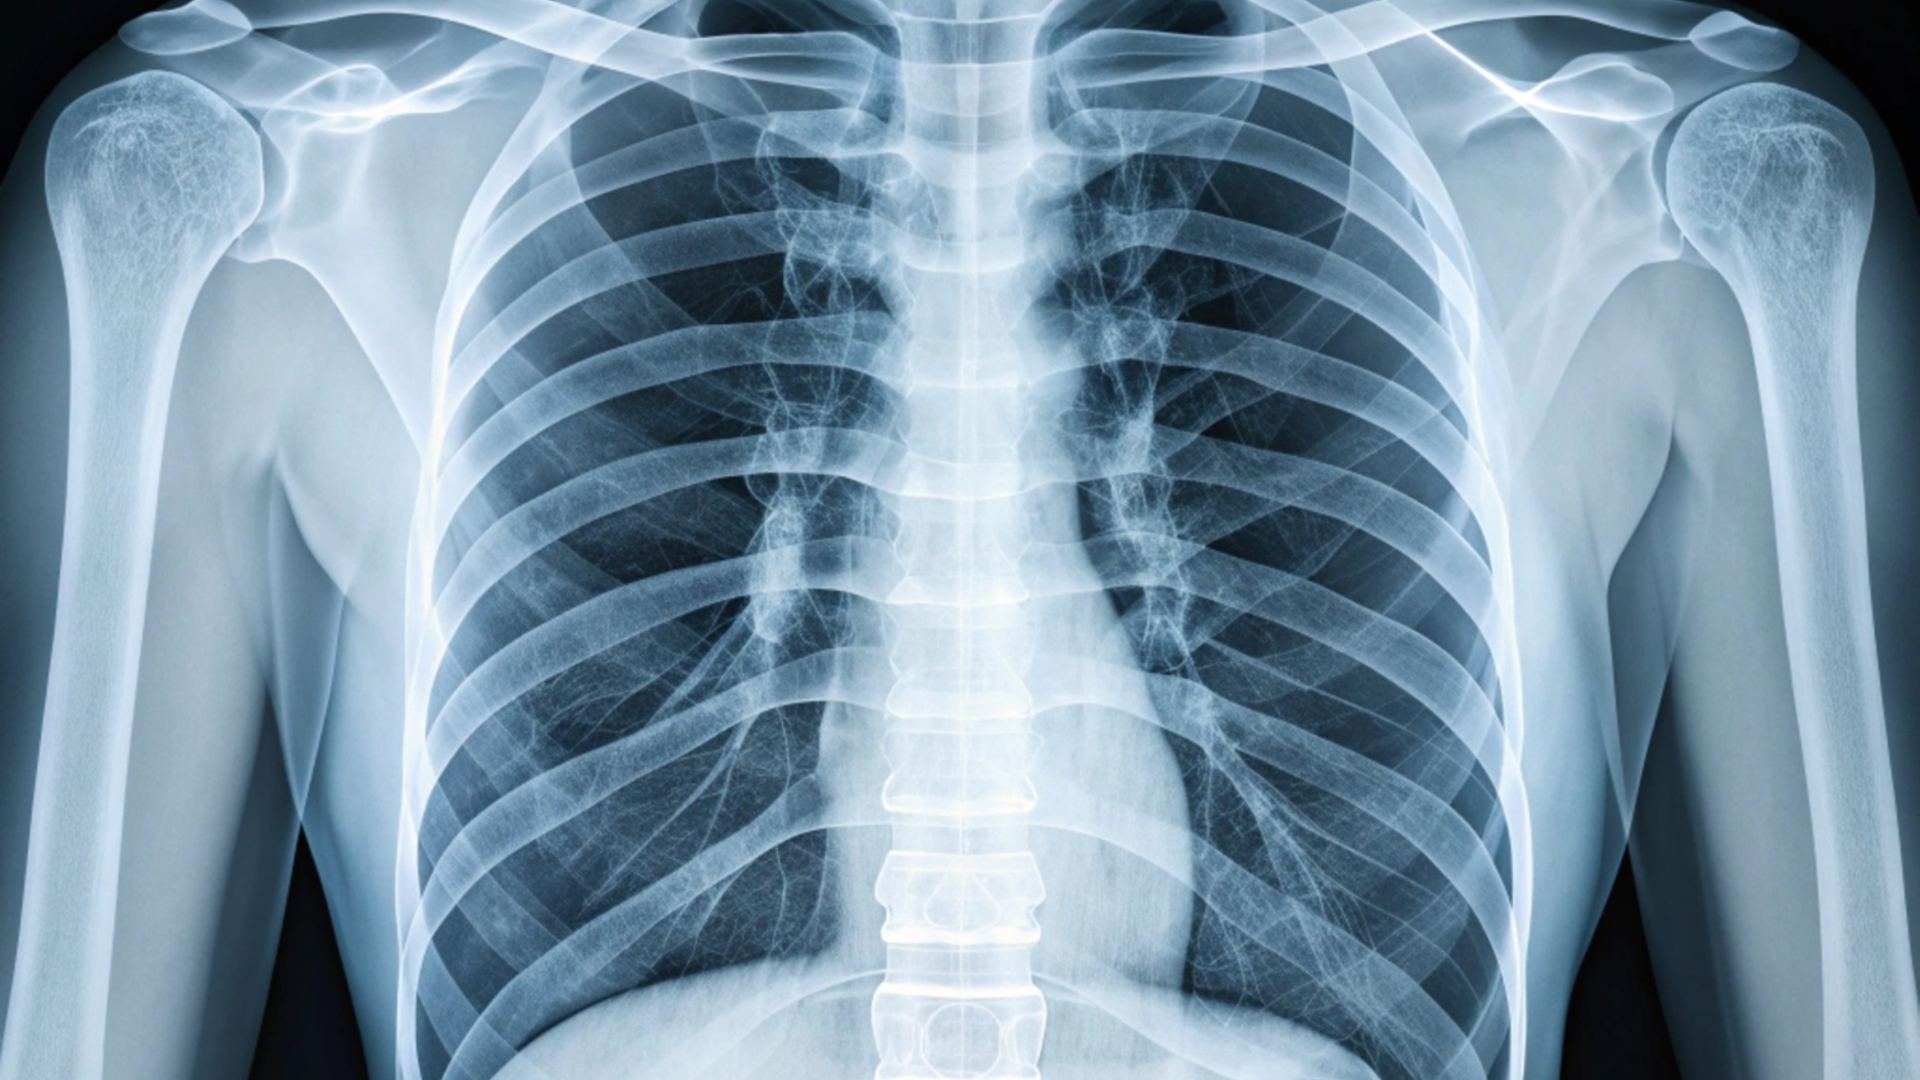

Thời gian hồi phục thường nhanh hơn so với gãy xương sườn, trung bình khoảng 4 - 6 tuần. Trong một số trường hợp, bác sĩ có thể yêu cầu chụp X-quang, MRI hoặc CT để xác định mức độ tổn thương và loại trừ các vấn đề nghiêm trọng hơn, như gãy xương hoặc tổn thương cơ quan nội tạng.